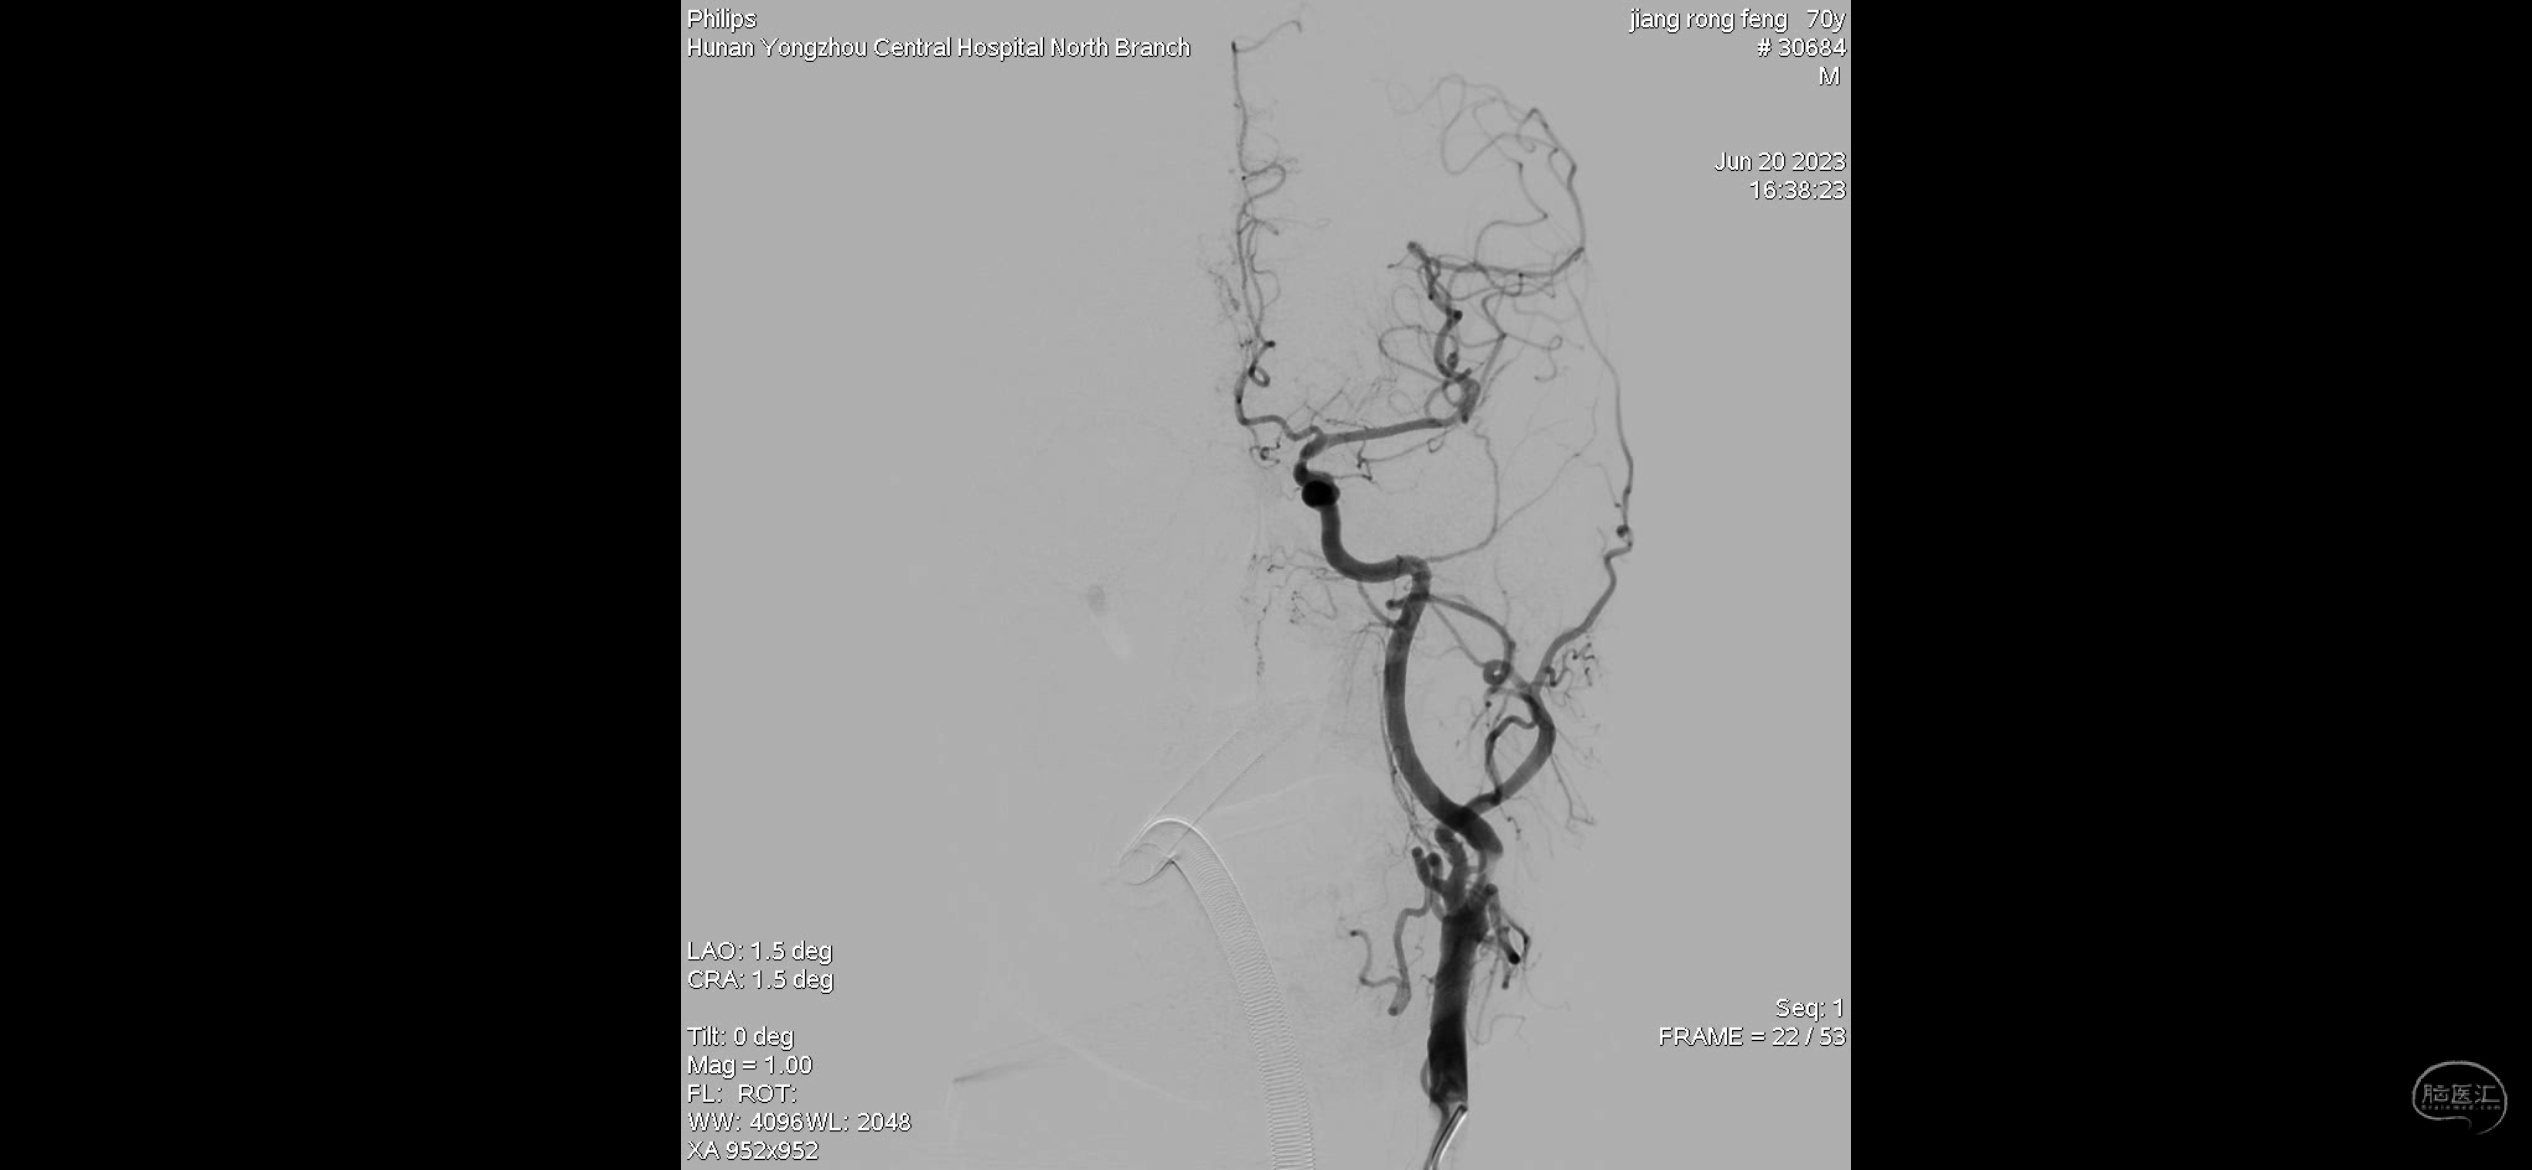

主动脉弓造影提示右侧颈内动脉闭塞。

右侧考虑颈内动脉C1段重度狭窄合并急性闭塞,眼动脉反流显影部分血管,右侧M1分叉部急性闭塞,右侧大脑前血流考虑血流灌注不足影响,且合并A2狭窄。

侧位造影

正位造影